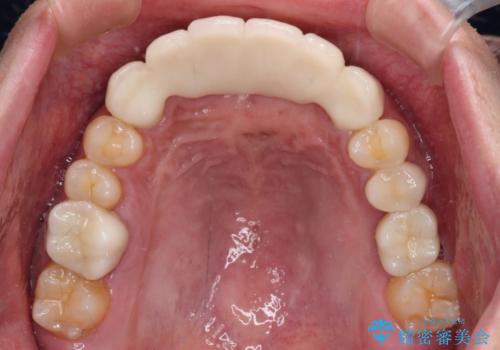

保存となった隣在歯も神経が失活していており、補綴治療が必要であったので、オールセラミッククラウンにて補綴治療することとしました。

奥歯には元々欠損があり、欠損に伴う咬合不正も認められたため、部分矯正を行った上でインプラント補綴治療も行うこととしました。